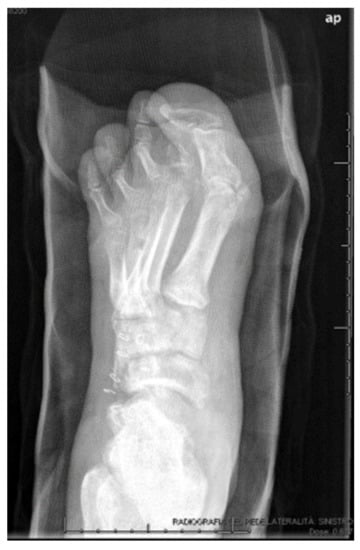

3.3. Lesions Involving Distal Tarsus & Talus